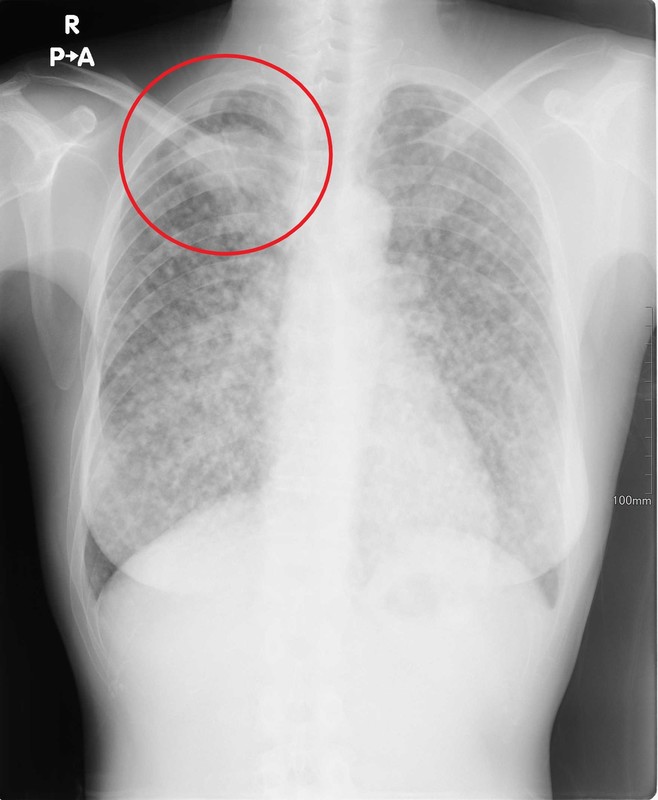

⑦肺癌

肺を発生起源とする原発性肺癌や他の癌からの転移による肺癌があります。

進行すると咳や痰(血痰)、胸部の違和感や痛み、呼吸困難・息切れ、呼吸不全などの症状を認めますが初期には無症状で経過します。

治療のためには早期発見が極めて重要であり、健康診断で胸部レントゲン検査を行う大きな目的の一つです。

胸部レントゲン検査では様々な位置に様々な大きさや形の陰影が認められ、CTでの精密検査を行って必要なら生検による診断へと進みます。

近年、喫煙とは無関係なタイプの肺癌も増えてきており喫煙の有無にかかわらず定期的な胸部レントゲン検査を受ける意義が大きくなっています。

↑それぞれ肺癌を疑う陰影(赤丸部分)を認めます。